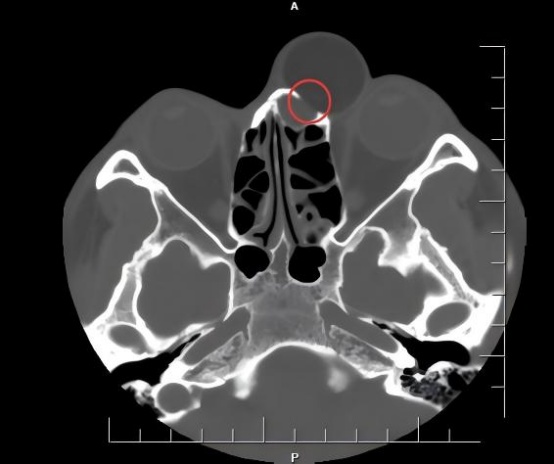

圆圈所指处为肿瘤压迫导致鼻骨受损